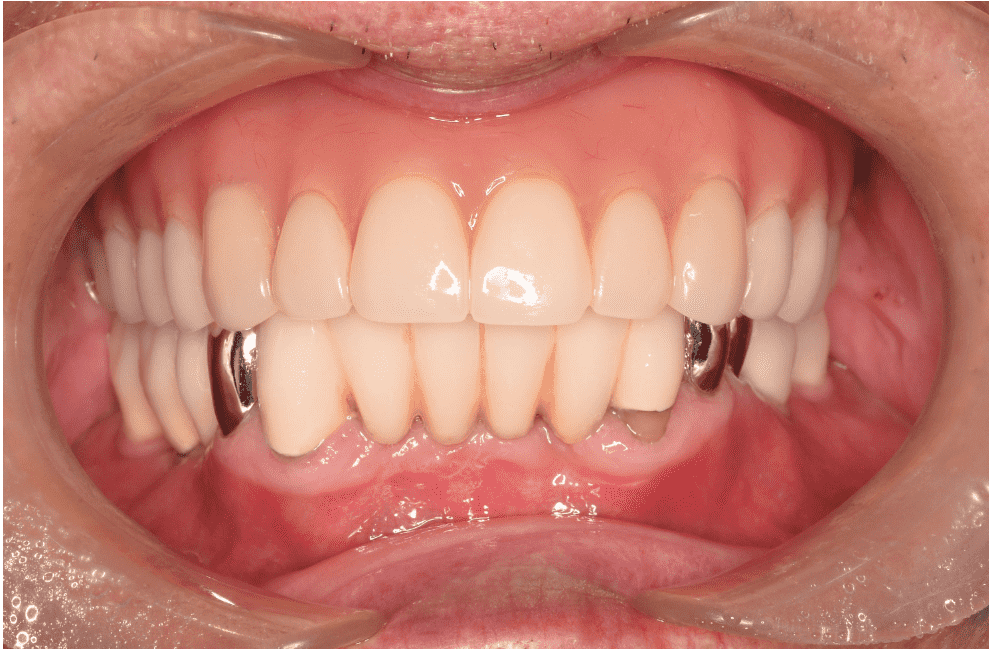

歯が折れた方へのインプラント治療

| 治療内容 | インプラント治療 |

|---|---|

| 年齢/性別 | 40代/男性 |

| 治療内容 | 折れてしまった歯を残すことが難しい状況だったので抜歯を行い、治癒のため3ヶ月待ってインプラント手術を行っています。その後、骨とインプラントが固まったことを確認し被せ物の処置をしています。当院ではほとんどの症例でデジタルでの型取りを行っています。インプラントを埋入した部位に型取り用のパーツをはめ、3Dスキャナーで型をとりジルコニアの被せ物を作製しています。最終的な被せ物はご自身の歯と変わらないような仕上がりとなっています。 |

| 治療期間 | 抜歯後の治癒期間含め、約6ヶ月 |

| 費用 | 473,000円 (税込み)(オペ代、仮歯代、被せ物代含む) |

| リスク/副作用 | 手術後の痛み、腫れ、インプラント周囲炎 |